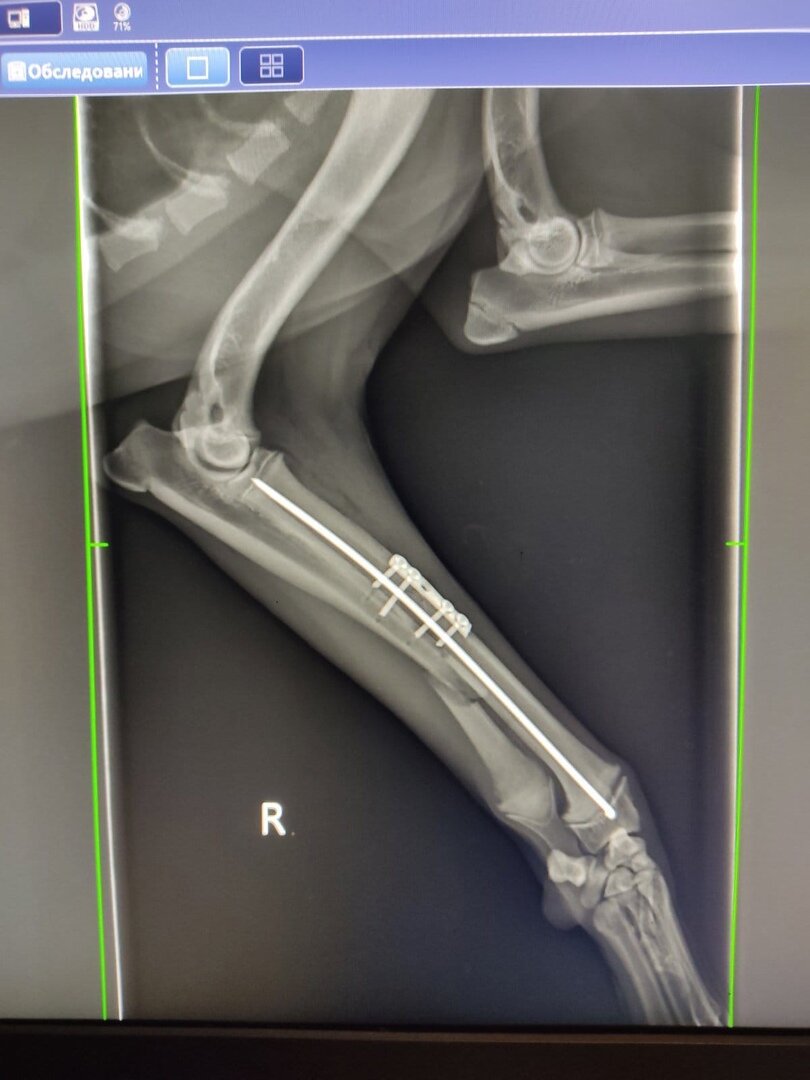

Подростка Софу сбила машина в районе ЖД, сломаны передняя и задняя лапки... Уже прооперирована.

Просим помощи в лечении Софочки! Это бездомный щенок и совсем нет никому дела до неё ….(((